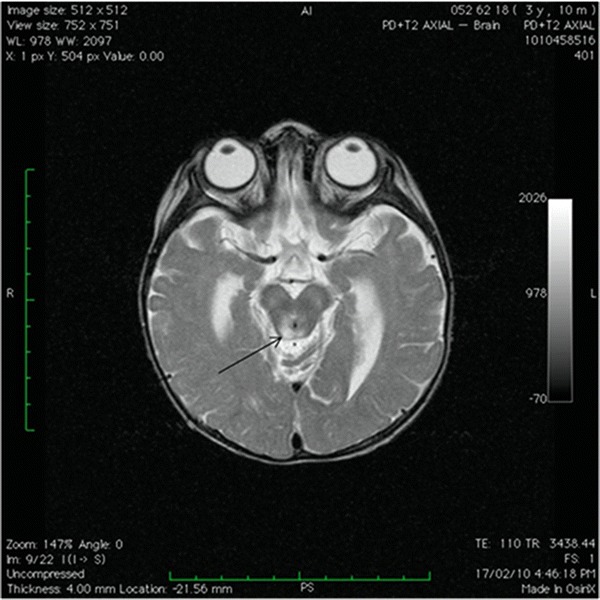

Urinalysis demonstrated marked generalized aminoaciduria, glycosuria and lactic aciduria along with elevated urinary orotic acid and Krebs cycle intermediates. A thoracic-abdominal CT angiography excluded aortic and renal artery stenosis and renal, adrenal and paraaortic masses. Cranial MRI was performed on day 5 of admission and demonstrated symmetrical hyperintensities on T2 weighted images in the tegmental area and in the peri-aqueductal grey matter (see Fig. 2). This was thought to represent changes characteristic of Leigh syndrome, which was confirmed by mtDNA mutation screening. This demonstrated the m.13513G>A mutation in the MT-ND5 gene of complex I; mutation load from leukocytes was 50%. Coenzyme Q10, thiamine, carnitine and idebenone were commenced

Fig. 2.

Cranial MRI: Axial T2 weighted image showing hyperintensities in the peri-aqueductal grey matter (arrow)